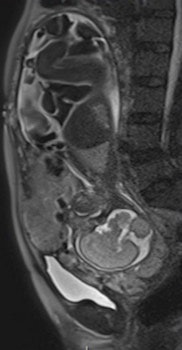

Their retrospective study included 25 pregnant women (mean age 35.16) -- 12 with histopathologically proven placental invasion and 13 without to act as a control -- who were investigated by prenatal MRI without IV contrast at three hospitals using three different 1.5-tesla MRI units (Magnetom Symphony, Siemens Healthcare; Intera, Philips Healthcare; Signa, GE Healthcare). The women underwent MR imaging between June 2007 and December 2009 after obstetrician referral for suspected placental invasion upon standard pregnancy ultrasound exams. The MRI protocols were similar and included T1-weighted volume interpolated gradient-echo MR sequences in the sagittal and axial plane, single-shot fast spin-echo T2-weighted MR sequences, and true fast imaging with steady-state precession in the axial, sagittal, and coronal planes.

Two senior radiologists with more than five years of practical experience in abdominal MRI and two junior radiologists with less than three years of abdominal MRI experience blindly and independently reviewed MR exams for six previously defined MR features described in the literature as useful for predicting placental invasion. The features included dark intraplacental bands on T2-weighted images, a focally interrupted myometrial border, heterogeneous intraplacental signal intensity, abnormal uterine bulging, "tenting" of the bladder, and infiltration of the adjacent pelvic organs.

In normal patients, the uterus presents as an inverted pear-shape organ. At MRI, the normal placenta appears as a soft-tissue structure, located along the uterine walls, with variable morphology and homogeneous, intermediate, signal intensity on T2-weighted images. In Alamo's study, T2-hypointense placental bands, a focally interrupted myometrial border, infiltration of the pelvic organs, and tenting of the bladder proved to be the best signs of predicting placental invasion.